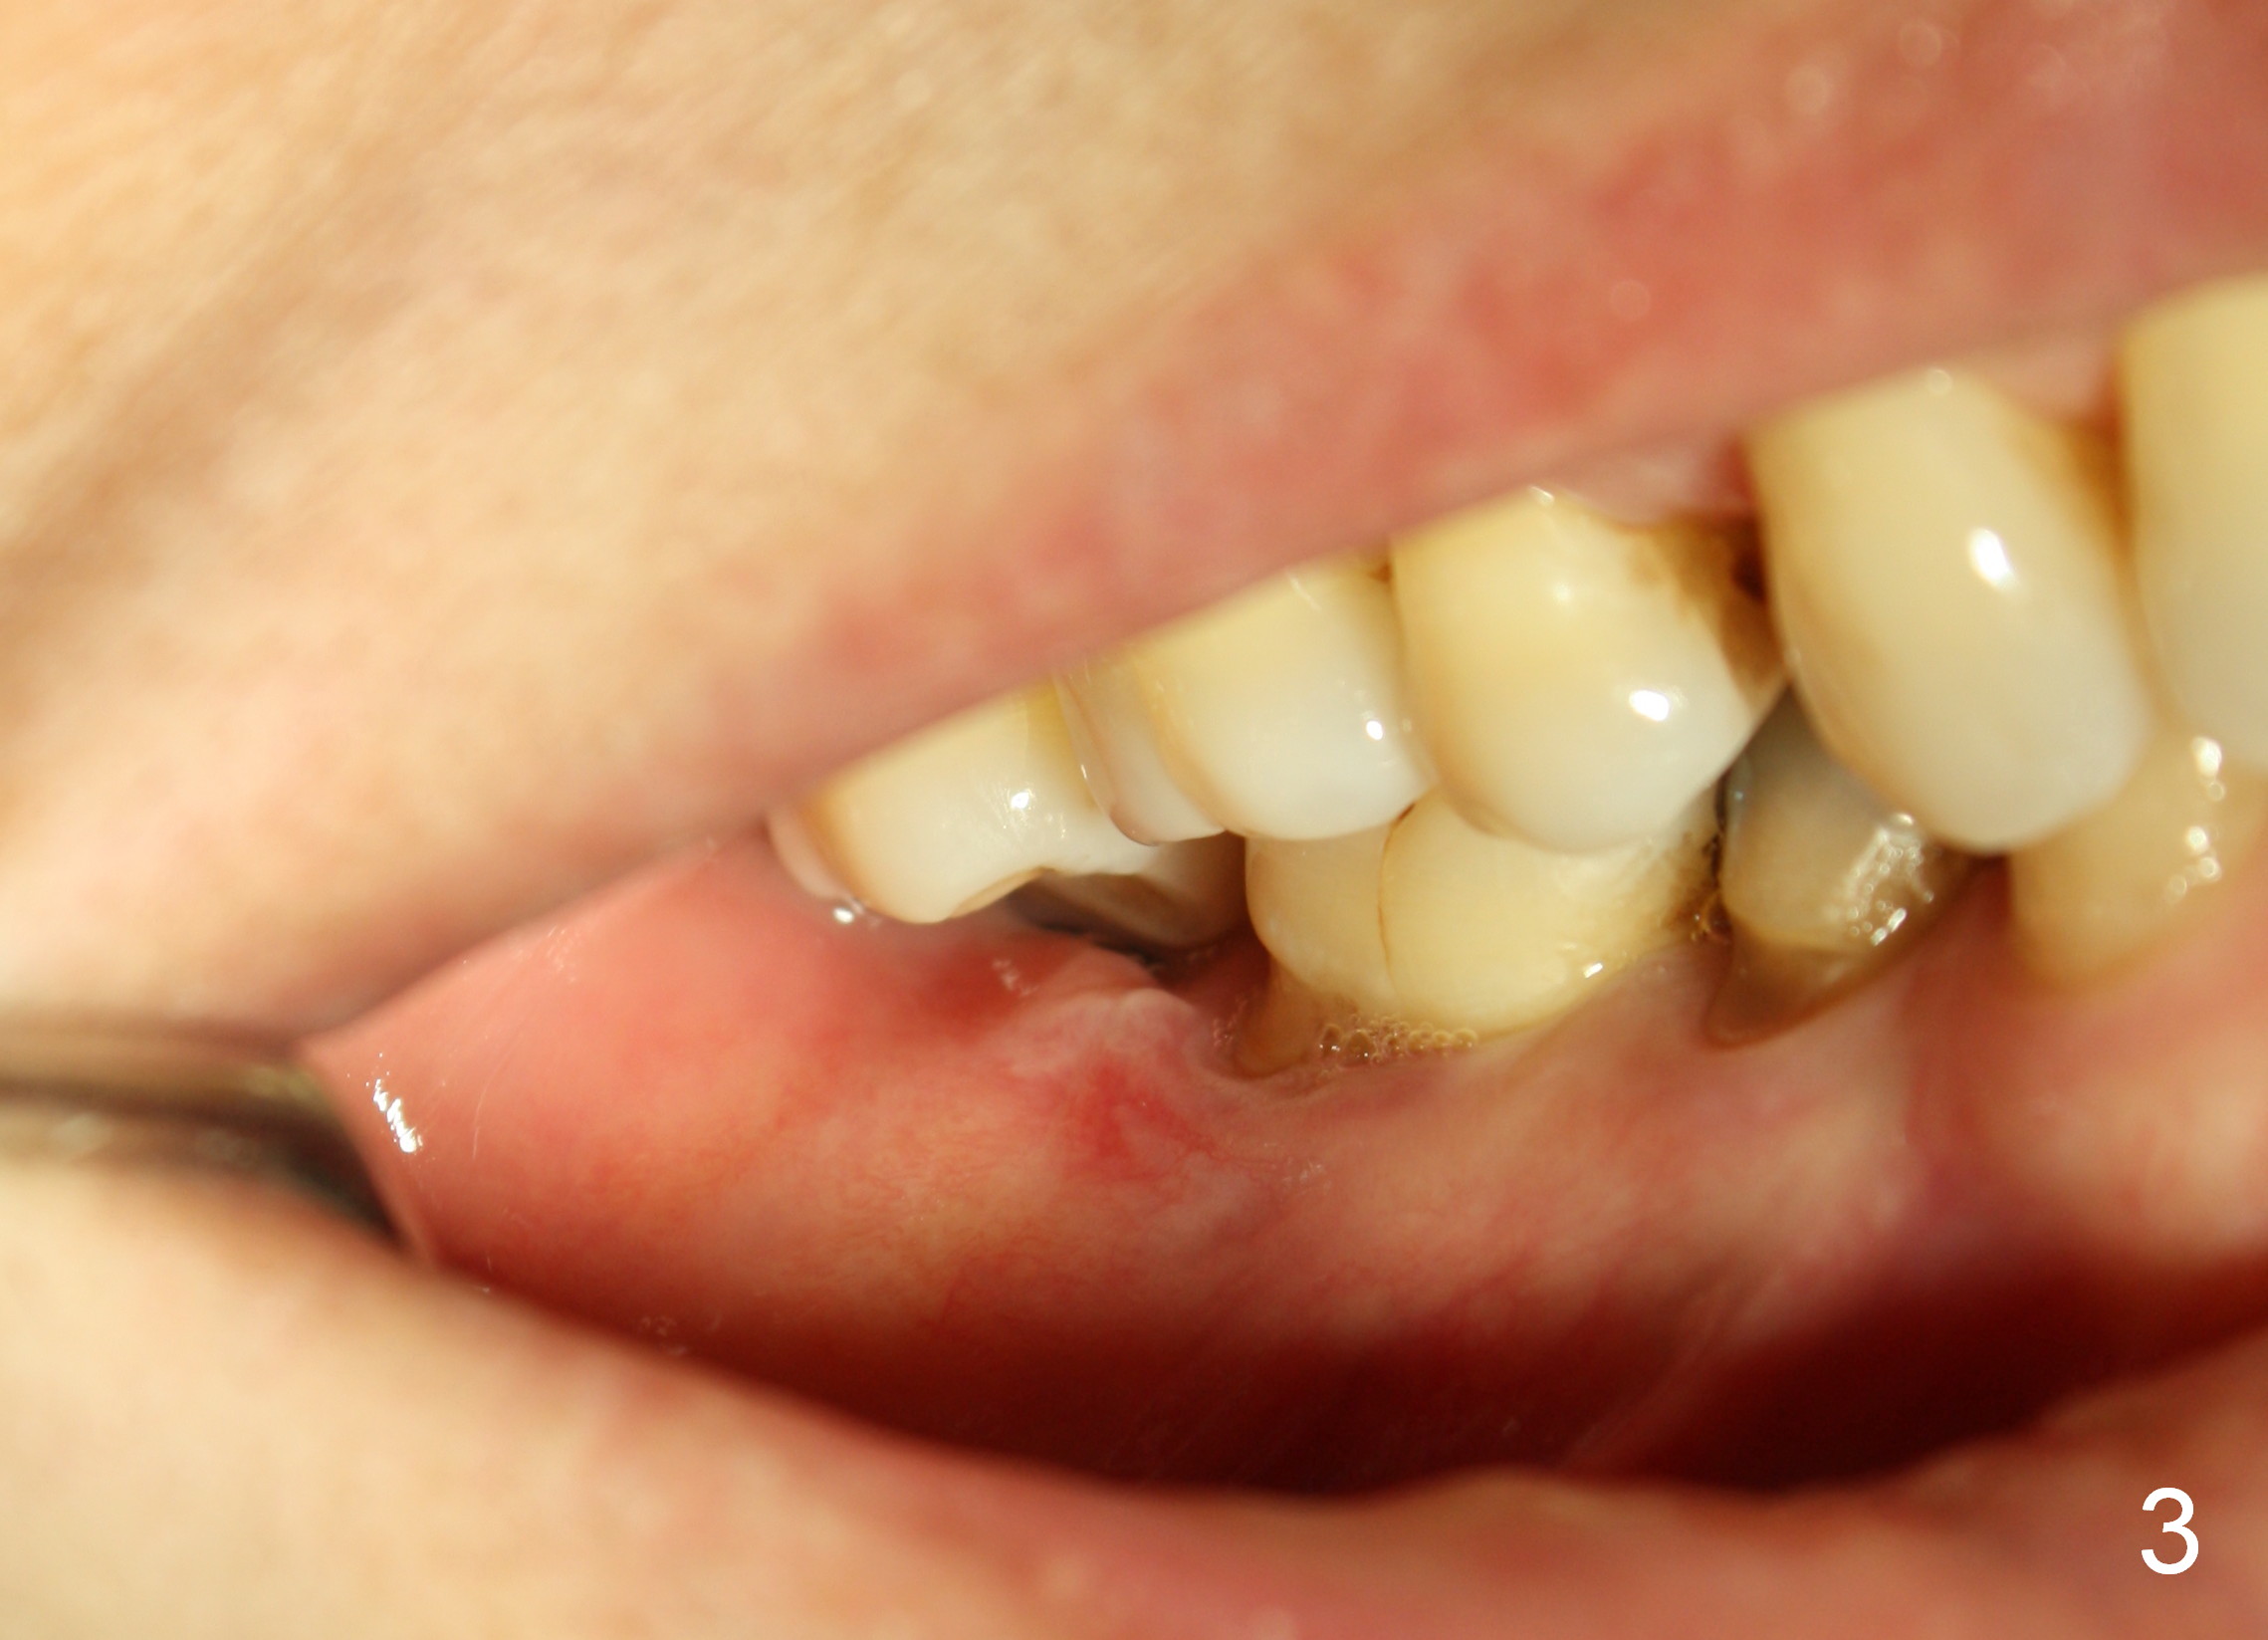

The wound of 2 stage implant surgery is found to be gapping 10 days postop with healing screw exposure 2 weeks postop. Exam at a month postop (Fig.1) shows that the mesiolingual cusp of the upper right 2nd molar is sharp (Fig.2 <) and inserted into the wound of the implant site (Fig.3). Two mini-implants are placed with immediate power chain retraction (Fig.4). The orthodontic intrusion is without effect; brackets are placed 4 months later (Fig.5). Two months later, the patient is diagnosed to have breast cancer. As a precaution for chemotherapy, the orthodontic device is removed. During chemotherapy, the patient returns once. The gingiva around the cover screw is mildly erythematous and edematous. After removing plaque from the cover screw with irrigation, the patient feels a little better. All of the orthodontic appliances are removed before she receives chemotherapy for breast cancer.